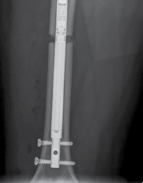

| Surgical techniques have changed in an attempt to minimise these complications. The use of intramedullary implants reduces fixator time and provides regenerate stability. Lengthening over a nail or lengthening followed by nailing still incorporates the use of an external fixator. The development of intramedullary lengthening nails eliminates the need for the external fixator. The initial designs utilised a ratchet mechanism that required rotation of the limb and bone segments to lengthen. A change in design was made where transcutaneous electrical energy drove a motor to improve control in lengthening. The latest and most popular implant is the Precice Intramedullary Lengthening Sysytem (NuVasive Inc., California). This is a magnet-operated telescopic internal lengthening device with an outer casing of titanium alloy (Ti-6Al-4V). A cylindrical rare earth magnet is connected to a gear box and screw shaft assembly within the nail. Two rotating rare earth magnets in an external remote controller (ERC) | |||

| Figure 15.14 Precice lengthening nail. | |||

| Figure 15.15 Growth arrest in a 12-year-old child. are held over the magnet within the nail, resulting in rotation of the implant magnet which can either lengthen or shorten the nail with sub-millimeter accuracy. Early results are favourable confirming faster regenerate healing times, less complications, better cosmetic results and more favourable patient outcomes compared to lengthening using an external fixator (Figures 15.14–15.17). | |||

Figure 15.16 Completion of lengthening (8 cm).

6 weeks post lengthening 3 months post lengthening

Figure 15.17 Consolidation (8 cm).